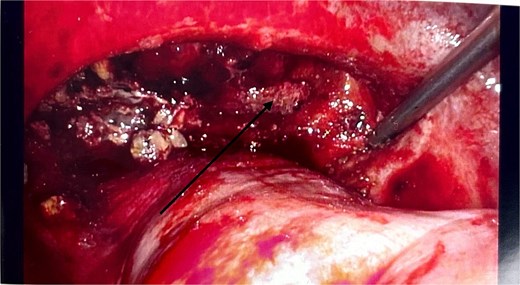

He had an emergency diagnostic laparoscopy. The intraoperative findings included four quadrant haemoperitoneum, ileus involving the stomach, small and large bowels, pelvic floor peritoneal nodules, and a cavity in the retro-colic posterior peritoneum over the pancreas extending into the pancreatic parenchyma with oozing of blood, as shown in Fig. 3.

Intraoperative laparoscopic picture showing a haemorrhagic cavity in the retroperitoneum extending into the pancreas (black arrow).